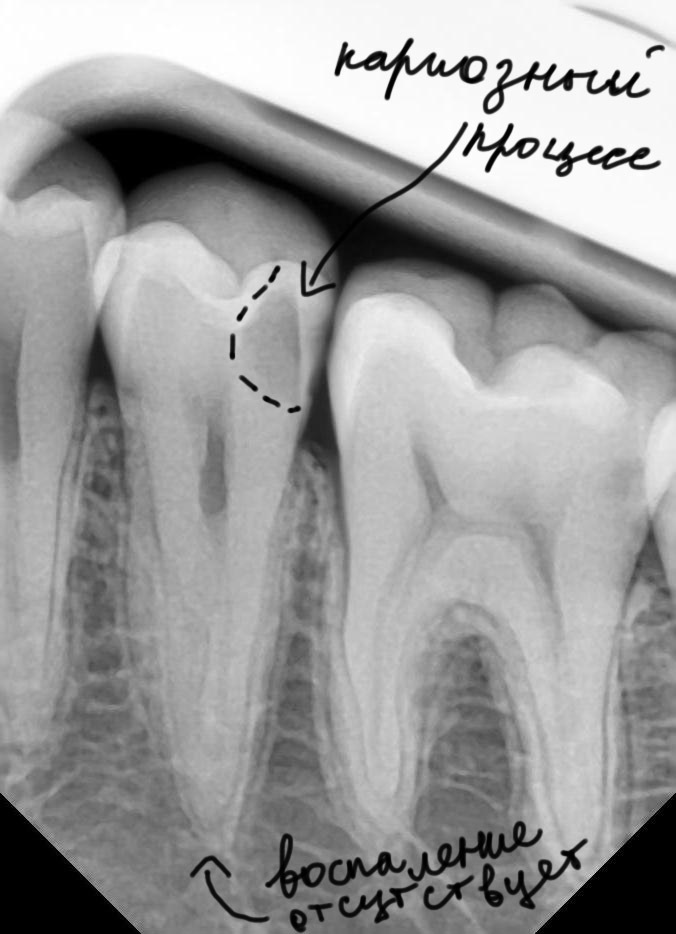

Рентгеновские снимки кариеса корня зуба

Раздел: Визуальные уроки